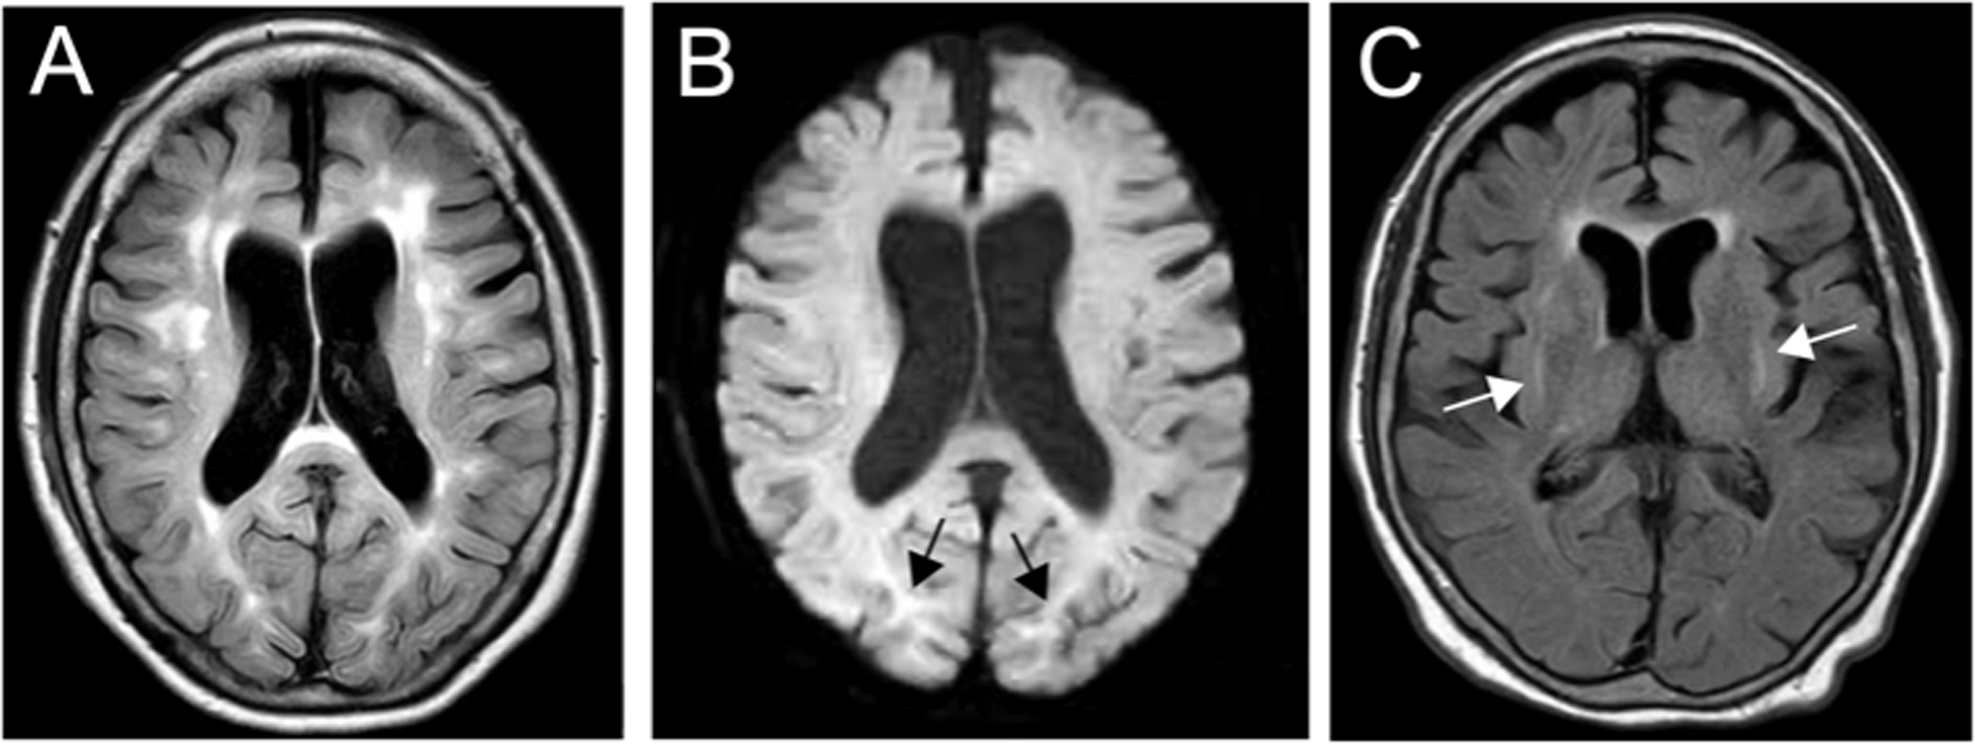

Fig. 1: Clinical and radiological features of the patient.

A FLAIR image showing periventricular hyperintensity and deep and subcortical white matter hyperintensity (axial; 1.5 T; TR, 8000 ms; TE, 100 ms). B DWI showing high-intensity signals (arrows) in the region of the corticomedullary junction in the bilateral occipital lobes (axial; 1.5 T; TR, 3732 ms; TE, 89 ms). C FLAIR image showing basal ganglia hyperintensity (axial; 1.5 T; TR, 8000 ms; TE, 100 ms).